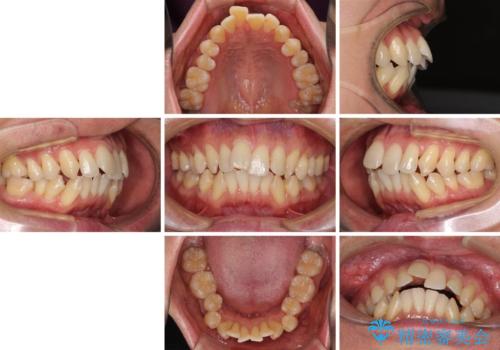

掃除しにくい前歯と閉じにくい口元 目立たないワイヤー装置での抜歯矯正

- 口元の閉じにくさと、前歯のでこぼこの歯並びを気にして来院された患者様です。

口元を積極的に引っ込めるために、上下左右の小臼歯計4本を抜歯することとしました。

叢生が強い場合、抜歯スペースが叢生を解消するために消費されるため、口元の突出感があまり改善されないことがあります。

今回の治療では、奥歯が前方に傾斜した歯並びだったため、奥に起き上がることで歯列が後方に移動し、横側からも口元が引っ込んだ感じが分かるほど改善されました。